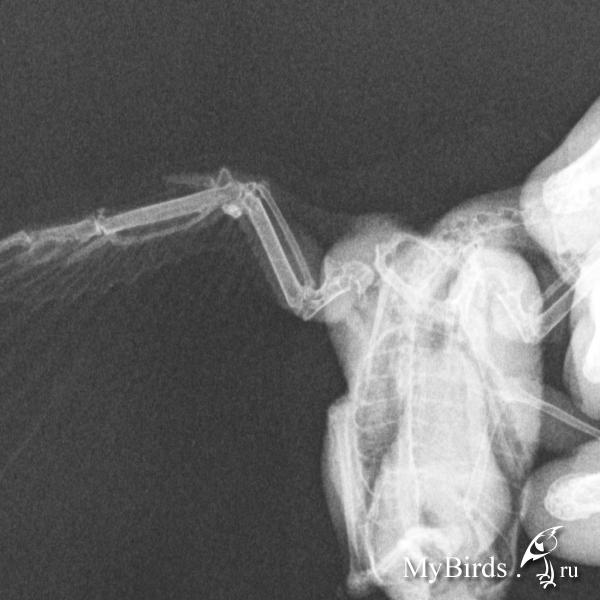

Рентгеновский снимок крыла птицы: анатомия и исследование